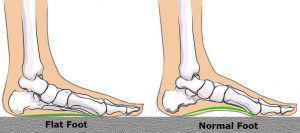

Per piede piatto, di fatto si intende un abbassamento della volta plantare di entità variabile sino al suo completo appiattimento, spesso associato a valgismo del retro piede (calcagno).

Il piede è naturalmente piatto nel bambino e in genere subisce un processo di formazione della volta plantare che si compie nei primi anni di vita. Solitamente questo atte ggiamento è considerato fisiologico fino a 8/10 anni, dopodiché si osserva una graduale maturazione che termina verso i 10/12 anni.

Il piede piatto può essere flessibile o rigido.

Nei bambini con il piede piatto, l’arco plantare scompare quando si è in piedi.

Per diagnosticare il problema, i bambini sono invitati ad alzarsi sulla punta dei piedi. Se l’arco riappare, il piede piatto viene chiamato flessibile e non sono più necessari ulteriori esami o trattamenti.